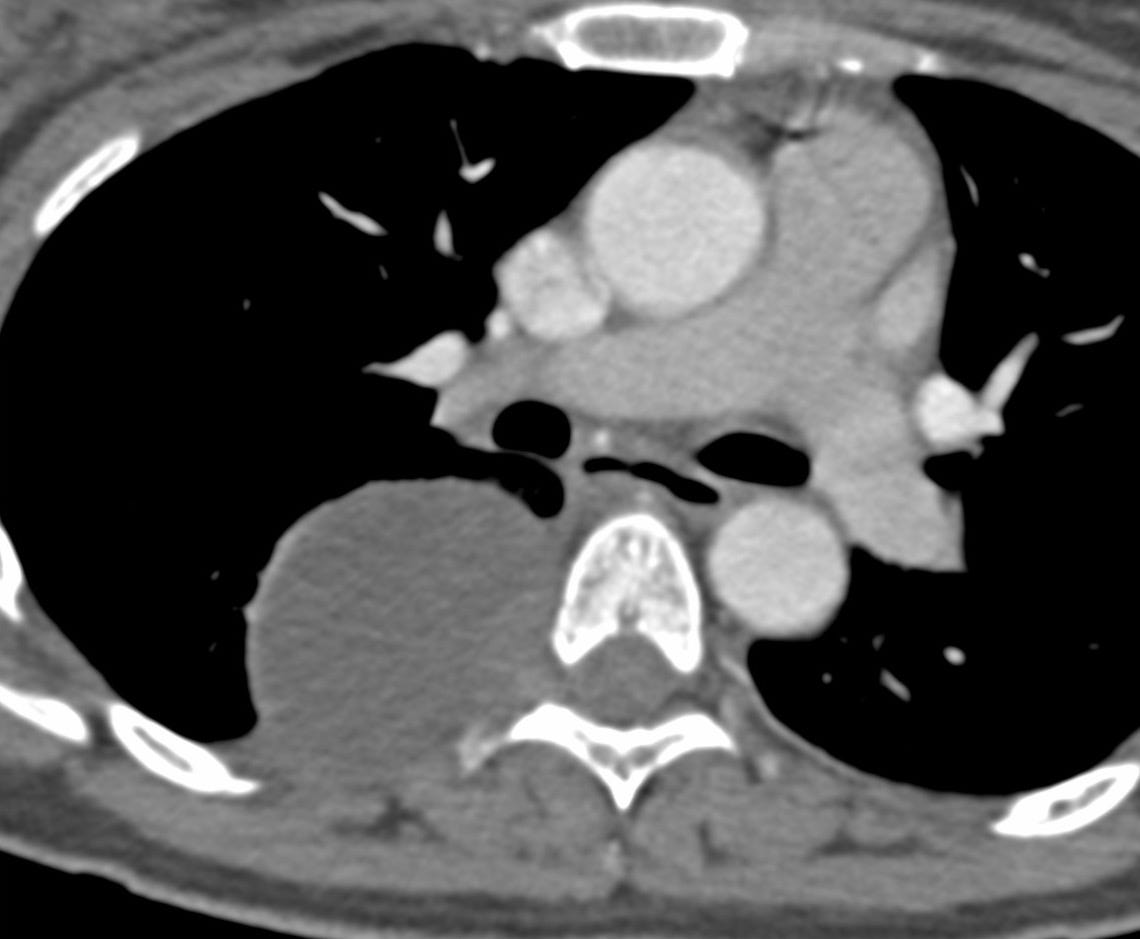

Case 23: An Incidental Posterior Mediastinal Mass

39-years old had a CT scan done for COVID-19, which picked up a mass in the chest

A 39-years old was found to have a mass in the chest on a CT chest done for COVID-19.